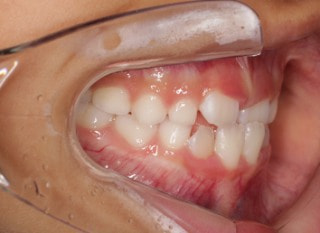

小児期の第二段階

治療中

終了時